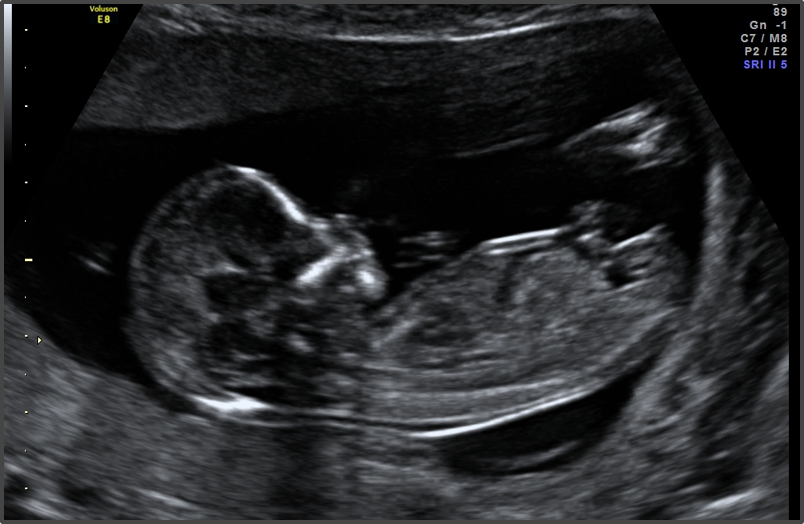

Sabe usted la fecha de la última regla?

SI

NO